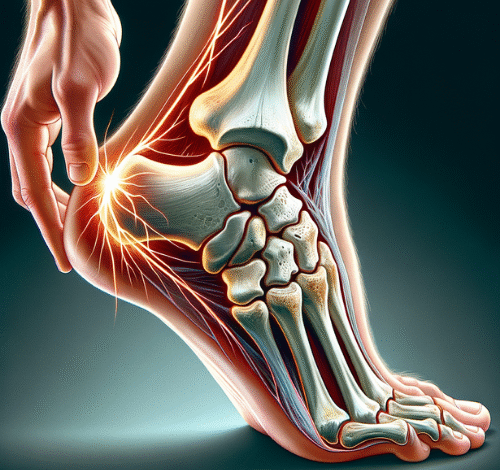

خار پاشنه چیست؟

خار پاشنه به تجمع کلسیم در قسمت زیرین استخوان پاشنه گفته میشود که به شکل یک زائده استخوانی ظاهر میشود. این زائده معمولاً در ناحیهای که رباطهای پا به استخوان پاشنه متصل میشوند، تشکیل میشود و میتواند باعث تحریک و التهاب بافتهای نرم اطراف شود. اگرچه این زائده استخوانی ممکن است تا حدود ۱.۲ سانتیمتر رشد کند، اما اندازه آن لزوماً تعیینکننده شدت درد نیست.

علائم خار پاشنه

- درد شدید در پاشنه پا: درد ناشی از خار پاشنه معمولاً در قسمت زیرین پاشنه حس میشود و ممکن است به سمت قوس پا نیز گسترش یابد.

- درد پس از استراحت: درد معمولاً پس از استراحت طولانی، مانند بیدار شدن از خواب یا نشستن طولانی مدت، بیشتر میشود و با شروع حرکت، کاهش مییابد.

- درد مزمن: در برخی موارد، درد خار پاشنه میتواند به صورت مزمن و مداوم باشد و در طول روز تداوم داشته باشد.

- تورم و التهاب: گاهی اوقات ممکن است ناحیه پاشنه متورم و ملتهب شود.